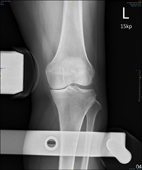

左圖:術前膝關節X光片;右圖:術後膝關節X光片。